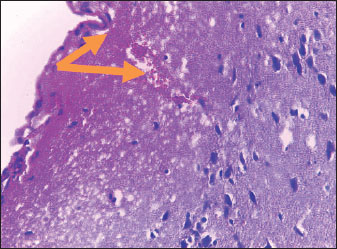

Brain of control group appeared normal structure of tissue with manifestation of Purkenji cells (Fig. 1), whereas sodium benzoate administration at low dose (200 mg/kg) occurred several histological lesions as hypertrophy of neurons (Fig. 2), pair nuclei arranged encompassed with clear space (Fig. 3), bleeding with degeneration of nerve cells (Figs. 4 and 5), respectively. In addition, lesions such as vacuolation, congestion, and accumulation of inflammatory cells were also evident (Figs. 6 and 7). However, severe histopathological lesions were observed following high-dose of sodium benzoate exposure, such as degeneration of neurons stained in dark blue (Fig. 8), prominent vascular duct with inflammation (Fig. 9), vacuolation, edema, and clear congestion as seen in Figures 1012, respectively.

Fig. 6. Points to the brain of sodium benzoate group (200 mg/kg): vacuolation of neurons (H&E) (100×).

Fig. 7. Points to the brain of sodium benzoate group (200 mg/kg): vacuolation of neurons (H&E) (100×).